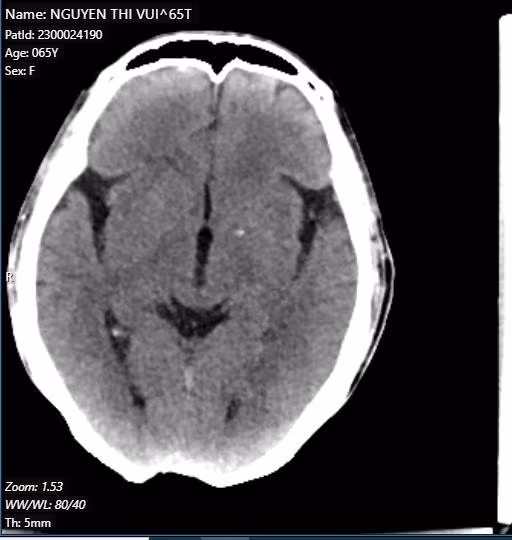

Sau khi được thực hiện các xét nghiệm cơ bản và chụp CT cho thấy ổ dịch hóa ở bao trong trái hướng đến tổn thương cũ, hình ảnh ăn mòn và khuyết xương chẩm vùng đường giữa; kết quả giải phẫu bệnh: Carcinoma vảy sừng hóa xâm nhập.

| Hình ảnh: Chụp cắt lớp vi tính sọ não của người bệnh có hình ảnh ăn mòn và khuyết xương ở xương chẩm |